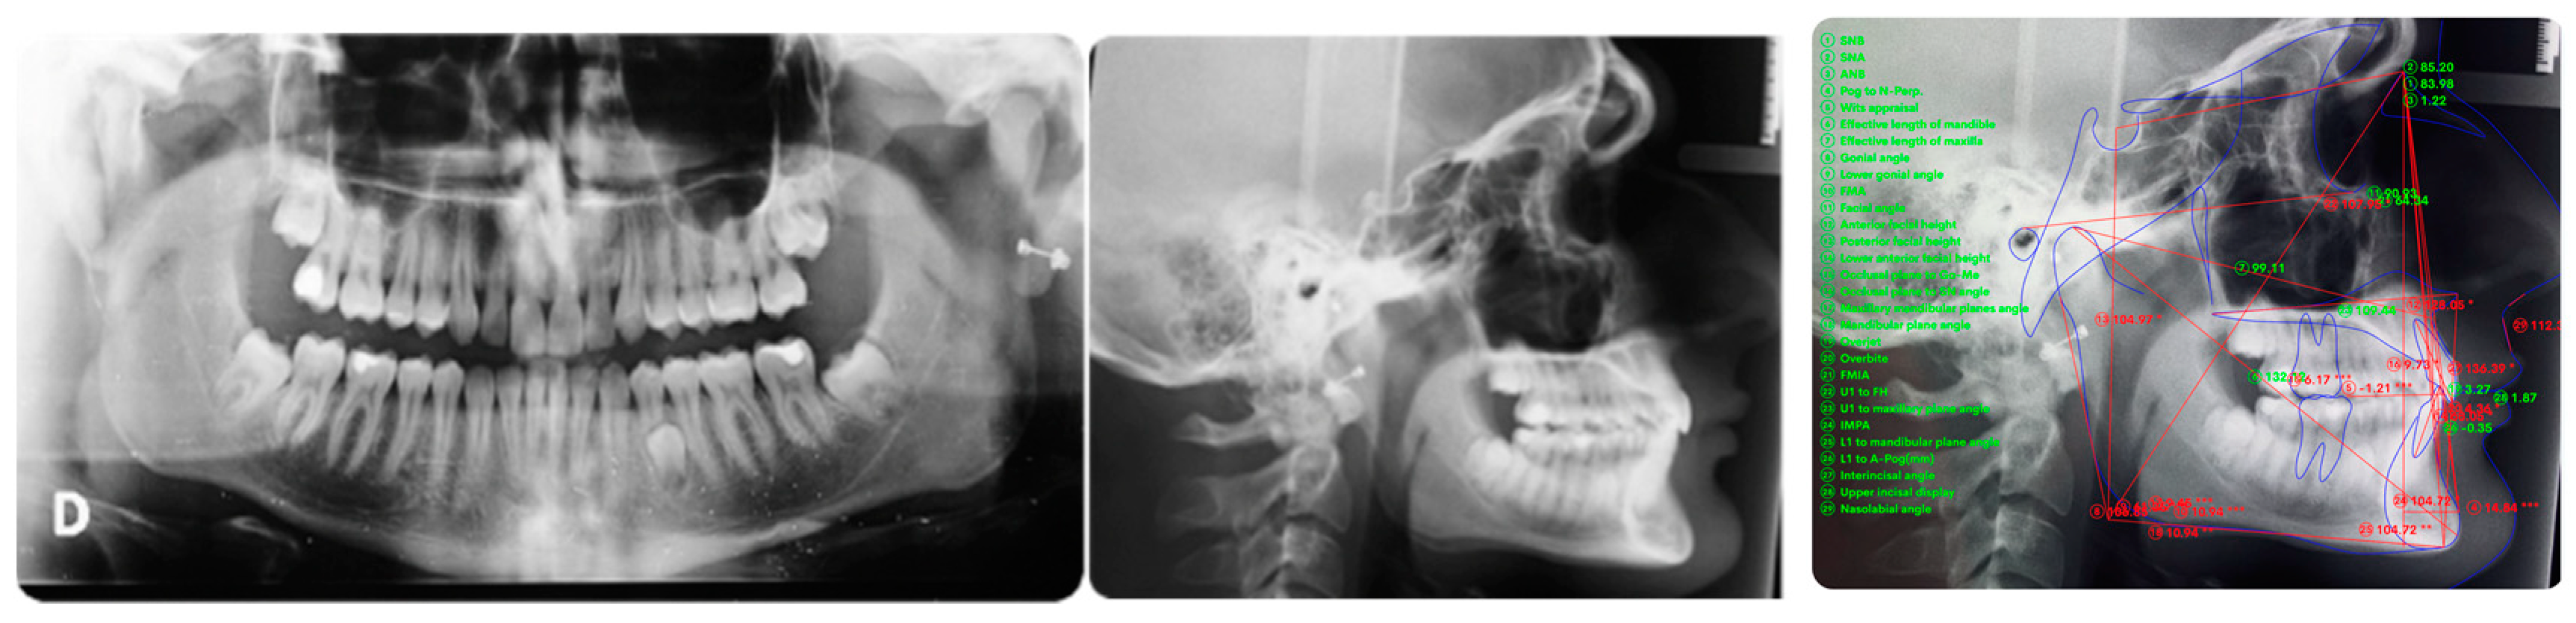

A 16-year-old male patient presented with a Class I occlusion, mild crowding, deep bite, and missing upper left cuspid with the absence of the respective deciduous. Light crowding can be detected in the maxillary arch, whereas no crowding was detected in the mandibular arch. The maxillary midline was coincident with the face and the mandibular midline. The radiographic analysis revealed a moderate impaction with a supernumerary tooth in the lower jaw between 3.5 and 3.4 ligually positioned and a skeletal Class I malocclusion with deep bite due to negative upper and lower incisors inclination.

Figure 2 panoramic and CBCT showing the moderate palatal 2.3 impaction. Lateral X-rays confirming a Class I skeletal and dental malocclusion with deep bite.

Figure 2.

Cephalometric analysis, panoramic and CBCT of the first patient. Lateral X-rays confirming a Class I skeletal and dental malocclusion with deep bite.

Torque finishing with aligners is the last stage of the treatment, which requires another refinement stage to obtain proper torque and inclination (Figure 6); in this case, a further stage of 18 aligners was necessary. The final occlusion is shown on Figure 7. The final X-ray analysis is presented on Figure 8.

Figure 8.

Post-treatment panoramic and lateral X-rays. The supernumerary lower tooth will be extracted following patient need in a second time. Cephalometric superimposition shows the torque correction and deep bite resolution.